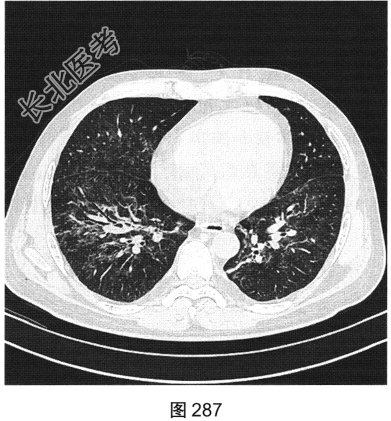

- [材料题] 患者男性,33岁,因“双下肢散在皮下出血点伴尿检异常3个月余,咳嗽、胸闷伴发热一周”就诊。患者脂肪肝、胆囊炎,服用莲葡双清片;随后几日内食用淡水鱼、鱿鱼、饮啤酒;5天后出现双下肢散在皮下出血点,未重视;10天后出现腹痛,在当地医院检查尿中有蛋白、定量不详,血常规检查正常,肾功能正常,应用醋酸泼尼松效果欠佳,行肾活检术,病理诊断:紫癜性肾炎,继发IgA肾病。患者每天静脉滴注甲泼尼龙0.5g,共3天,后改为口服甲泼尼龙28mg/d,共35天。一周前着凉后出现咳嗽、胸闷伴发热,体温达39.1℃,于当地医院抗炎治疗效果欠佳,遂来本院。实验室检查:血白细胞计数6.92×109/L,中性粒细胞0.845,CRP为2.7mg/dl。患者PP65阳性。胸部CT检查如图284~图287所示。

- 多项选择题3.常用的临床检测方法包括( )

A、活检

B、痰检病原菌

C、抗体检测

D、mRNA蛋白检测

E、体液检测

F、抗原检测

- 多项选择题4.该病的常见影像表现有( )

A、空洞

B、双肺磨玻璃影

C、淋巴结增大

D、实变

E、小叶中央结节一树芽征

F、血管支气管束和小叶间隔增厚